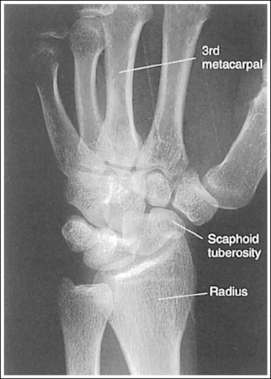

See Figure 4-29 and Box 4-11.

Contrast and density are adequate to demonstrate the scaphoid fat stripe.

• Significance of the scaphoid fat stripe. The scaphoid fat stripe is one of the soft tissue structures that should be visible on all PA wrist projections (Figure 4-30). It is convex and located just lateral to the scaphoid in an uninjured wrist. A change in the convexity of this stripe may indicate to the reviewer the presence of joint effusion or of a radial side fracture of the scaphoid, radial styloid process, or proximal first metacarpal.

The wrist is positioned in a PA projection. The radial and ulnar styloids are at the extreme lateral and medial edges, respectively, of each bone. The radioulnar articulation is open, and superimposition of the metacarpal bases is limited.

• Rotation of the wrist and forearm is controlled by the position of the hand, elbow, and humerus. A PA projection is accomplished by abducting the humerus until it is positioned parallel with the IR and the elbow is in a lateral projection. The hand is then pronated, placing the wrist in a PA projection (Figure 4-31).

The wrist has been externally rotated to a 45-degree PA oblique projection. The trapezoid and trapezium are demonstrated without superimposition, and the trapeziotrapezoidal joint space is open. The scaphoid tuberosity and waist are demonstrated in profile. Only a small degree of trapezoid and capitate superimposition is present.

• To accomplish a PA oblique wrist projection, begin with the wrist in a PA projection, with the humerus and the forearm on the same horizontal plane. Externally rotate the hand and wrist until the wrist forms a 45-degree angle with the IR (Figure 4-35). When judging the degree of wrist obliquity, it is best to view the wrist and not the hand. The obliquity of the hand and wrist are not always equal when they are rotated, especially if the humerus and forearm are not positioned on the same horizontal plane for the image.

• Determining the accuracy of wrist obliquity. On a PA wrist projection (see Image 39), the trapezoid and trapezium are superimposed. Placing the wrist in a 45-degree externally rotated PA oblique projection draws the trapezium from beneath the trapezoid, providing clear visualization of both carpal bones and the joint space (trapeziotrapezoidal) between them. The PA oblique projection also rotates the scaphoid tuberosity and waist into profile. The relationships between the trapezoid and trapezium and the trapezoid and capitate are used to discern an accurate PA oblique wrist projection. If the wrist is underrotated, the trapezoid and trapezium are superimposed, the trapeziotrapezoidal joint space is obscured, and the trapezoid demonstrates minimal capitate superimposition (see Image 40). If wrist obliquity is more than 45 degrees, the trapezium demonstrates minimal trapezoidal superimposition, the capitate is superimposed by the trapezoid, and the trapeziotrapezoidal joint space is obscured (see Image 41).